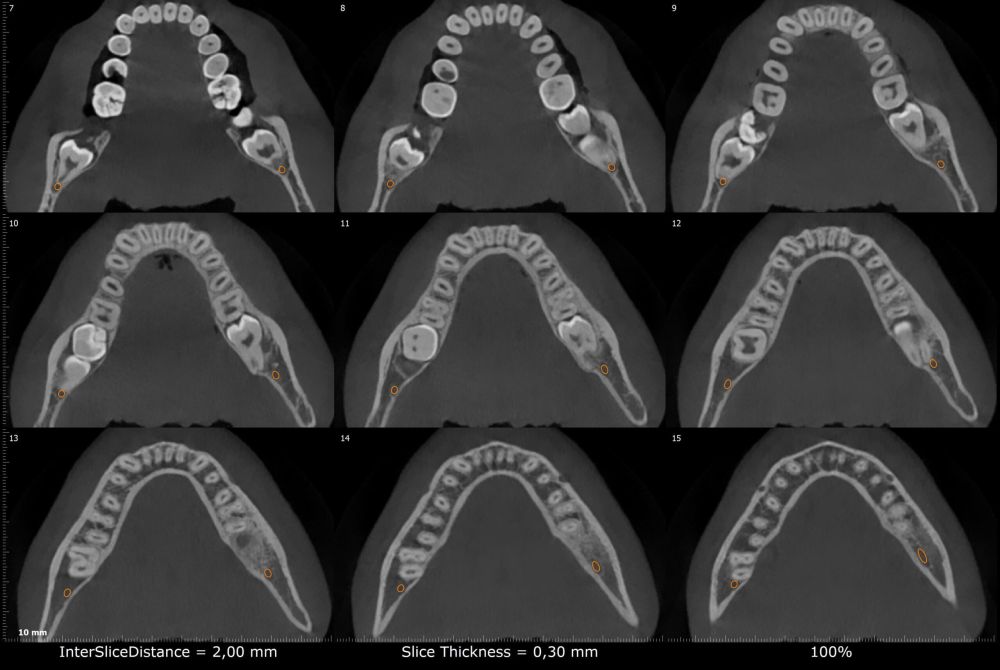

Métodos: Se presenta el caso clínico de un paciente varón de 18 años en el que, tras la realización de una CBCT de la arcada mandibular, se observó la retención de los segundos molares mandibulares permanentes junto con los terceros molares mandibulares.

Methods: We present the case of an 18-year-old male patient in whom, after performing a CBCT of the mandibular arch, retention of the permanent mandibular second molars was observed, along with the mandibular third molars.